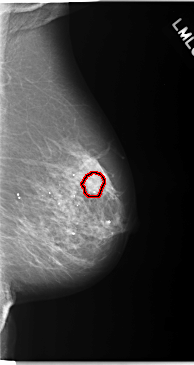

C_0093_1.LEFT_CC

LEFT_CC LINES 5912 PIXELS_PER_LINE 3048 BITS_PER_PIXEL 12 RESOLUTION 50 OVERLAY

FILE: C_0093_1.LEFT_CC.OVERLAY

TOTAL_ABNORMALITIES 1

ABNORMALITY 1

LESION_TYPE CALCIFICATION TYPE AMORPHOUS DISTRIBUTION CLUSTERED

ASSESSMENT 5

SUBTLETY 4

PATHOLOGY MALIGNANT

TOTAL_OUTLINES 1

BOUNDARY